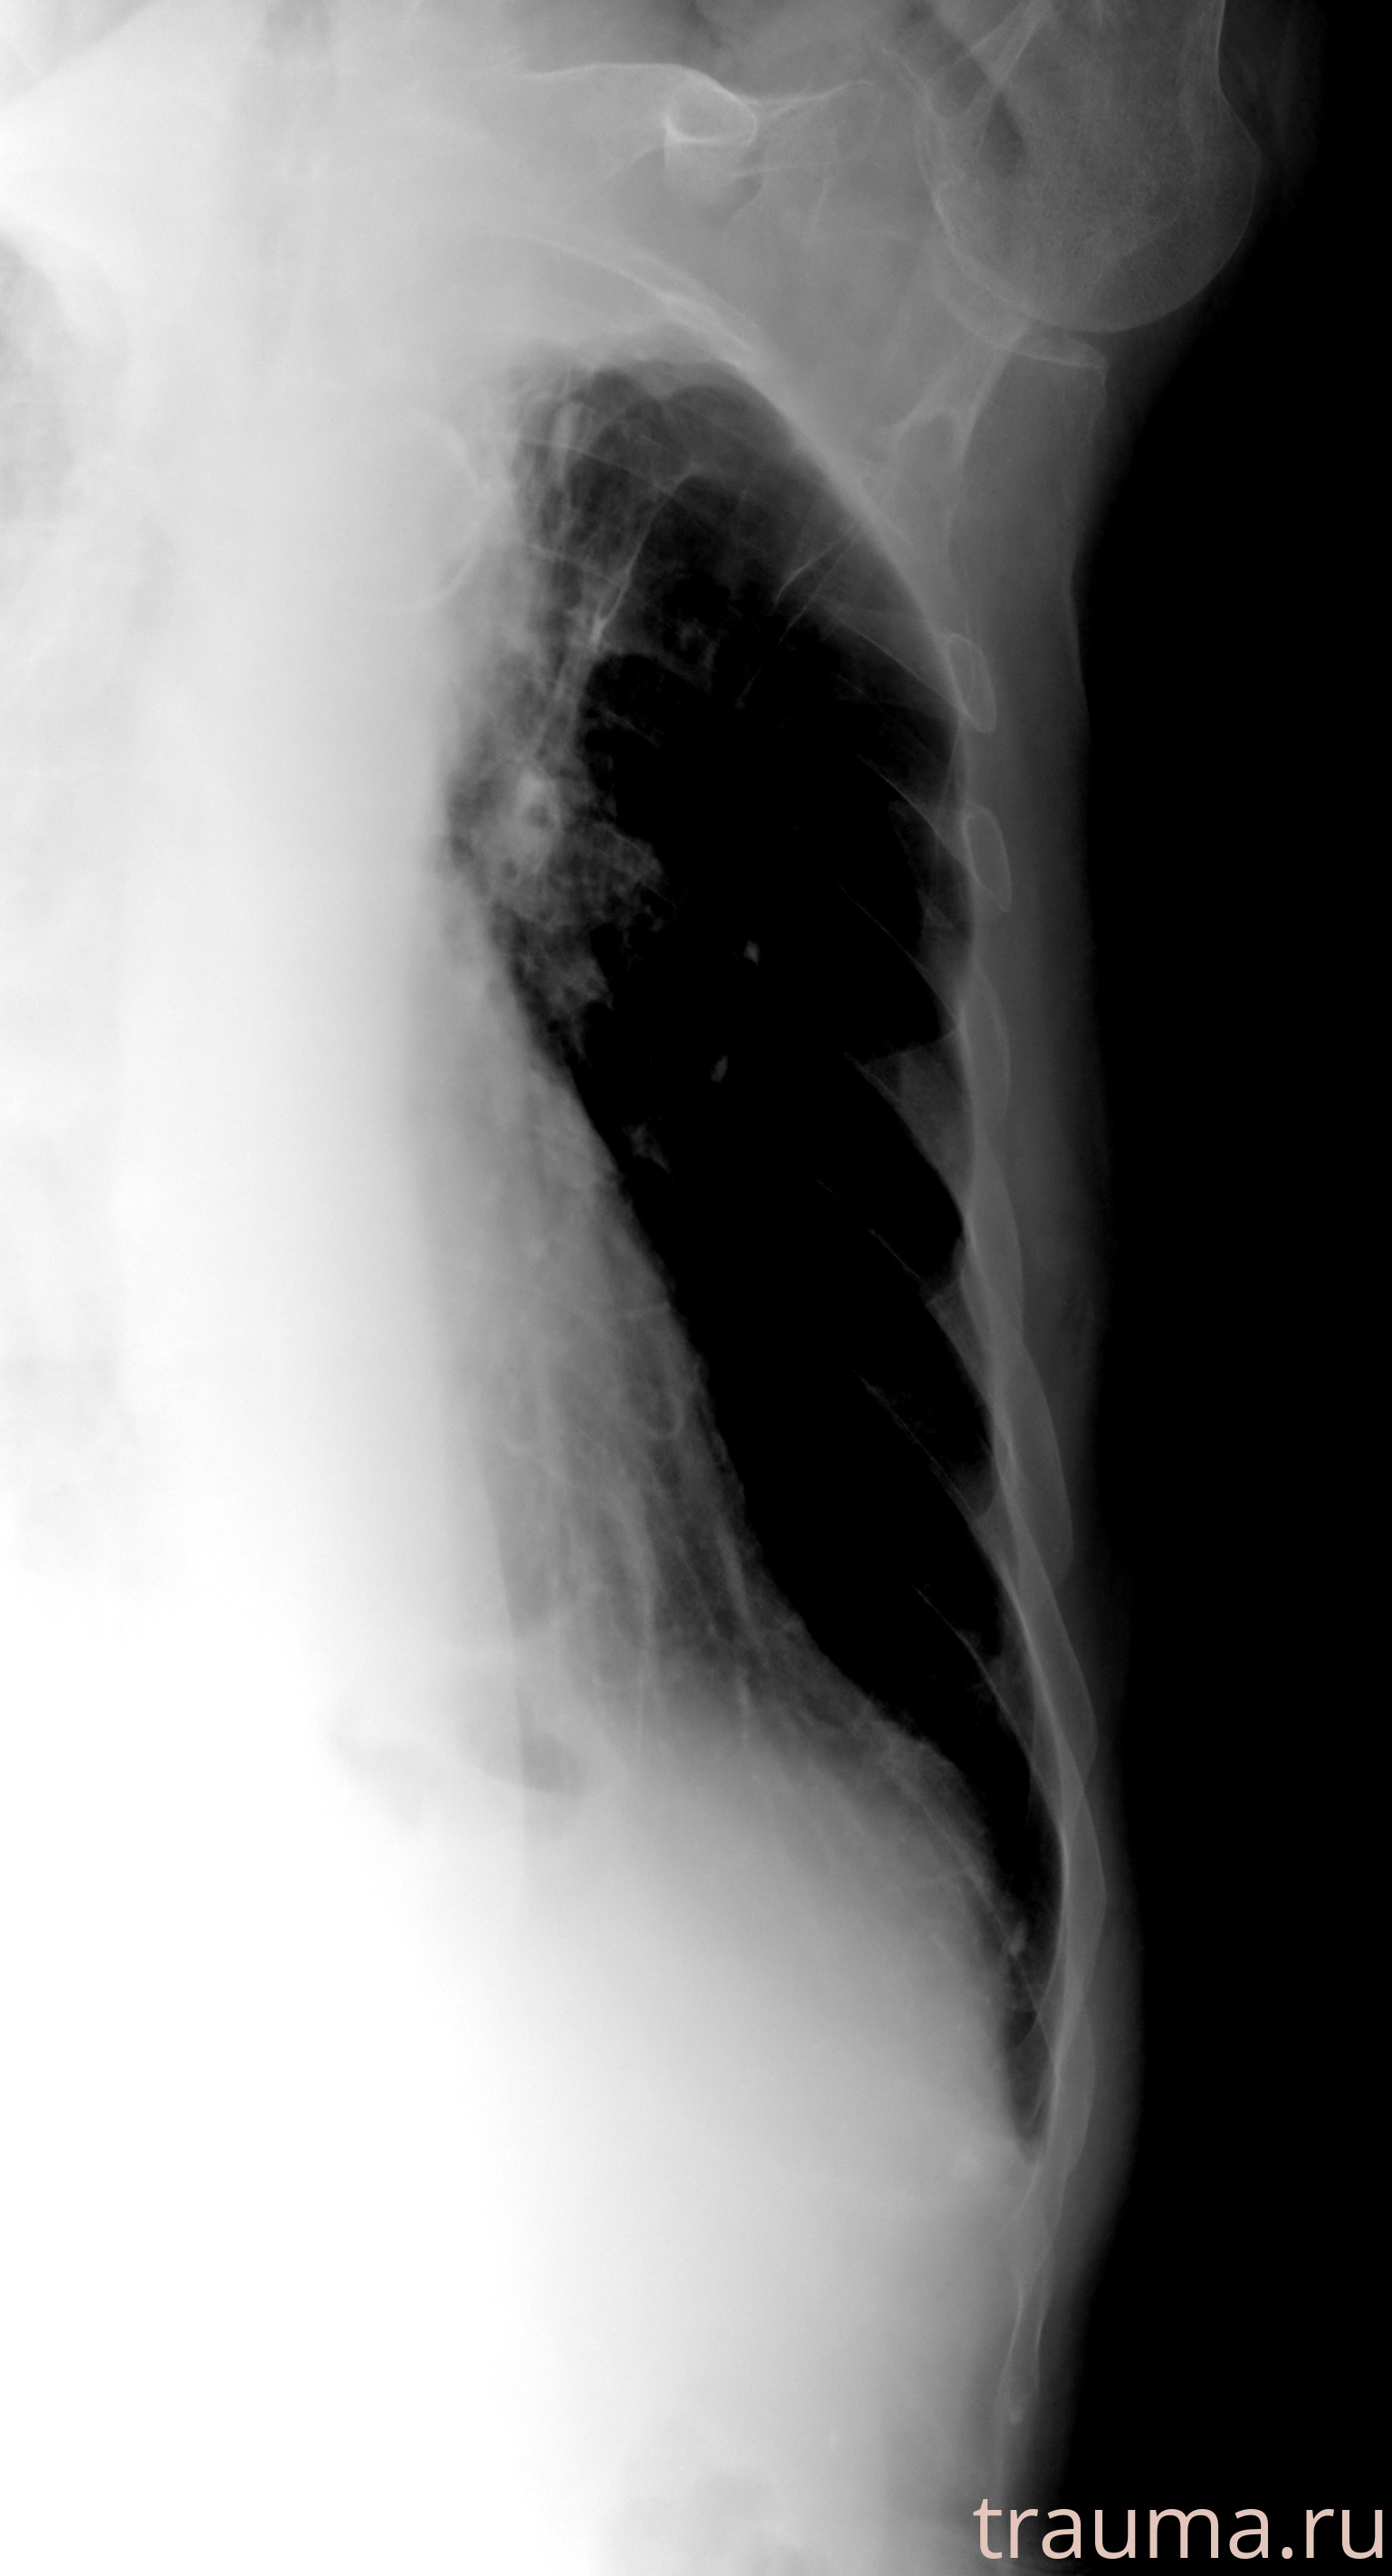

Рентген на дому: по вашему адресу приезжает врач-рентгенолог, травматолог-ортопед с мобильным рентгеновским аппаратом, проводит диагностику травмы или заболевания, делает необходимые рентгенограммы, дает рекомендации по дальнейшему лечению. Получить качественные снимки в домашних условиях возможно благодаря уникальной методике, разработанной МосРентген Центром для института  Склифосовского